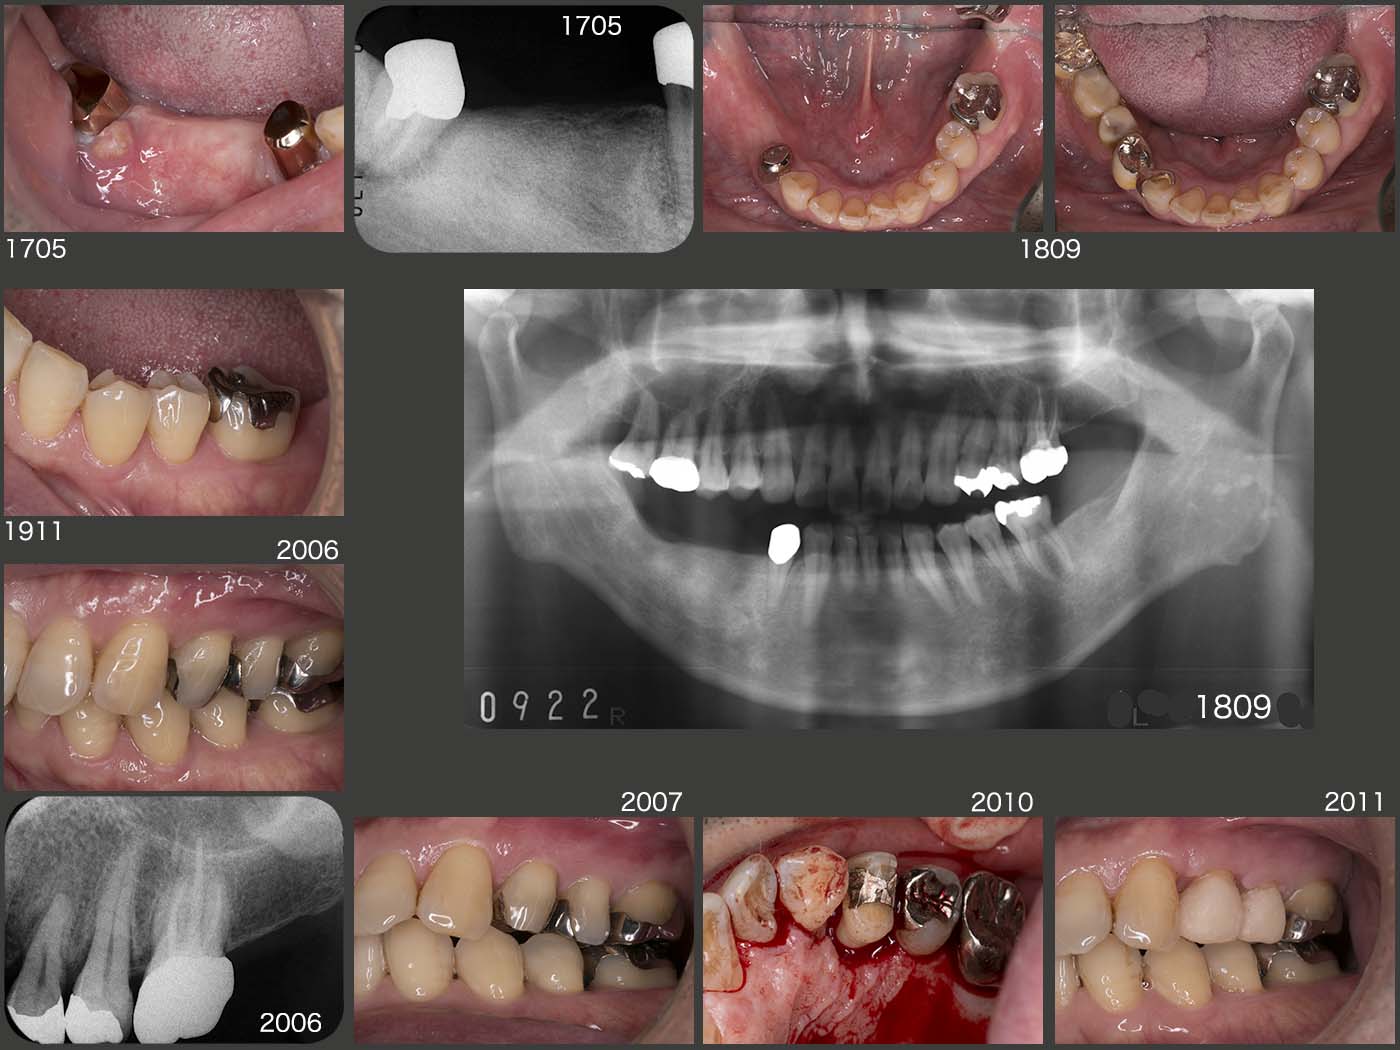

私が歯科医師になって2年目に治療した患者さん.1981年に右下ブリッジを自分で技工を行い,装着した.いわゆるロング・スパン・ブリッジである.暫くお目にかからなかったが,私が歯科医院を開業したのを機に,14年振りに95年11月に来院した.(中段パノラマX線写真)

2005年に左下7を歯根破折で失ったが,義歯を装着しないまま経過した.スライド下段は10年10月の状態.

2011年8月,歯根破折が原因で左上4を抜去し,12年2月に③4⑤のブリッジを装着した.ここで,左側大臼歯部でも咀嚼してもらいたいため,12年10月,左下にコーヌス義歯を装着した.(スライド上段)

この患者さんの習慣性咀嚼側は左側と思われる.だからこそ右下のロング・スパン・ブリッジが30年以上保ったといえる.さらに,ブリッジのポンティックを極端に小さくしたことが,左側咬みを助長したと思われる.13年7月,右下ブリッジのマージン部にう蝕がみられたのを機に,作り直しに同意していただいた.14年,右下に,可撤式ブリッジ(コーヌス義歯)を装着した.

この症例のようなロング・スパン・ブリッジにおいて,ポンティックの大きさを普通に作れば,ブリッジの支台歯の荷重負担に繋がるし,逆に小さく作れば反対側の歯の負担を助長する.バランスがとれた大きさにするのは難しいと痛感すると同時に,その際は咬合力の大きさ,有髄か否か,咀嚼側の見極め等,よく考えて製作することが重要である.

その後,2018年5月に左下5に6mm歯周ポケットが急に生じたため,歯根破折と診断した.しかし自覚症状がなく,患者さんの希望で暫く経過をみることとなった.12月,左側で咬みづらくなり,右側ばかりで嚙んでいるためか,デンタルX線写真より右下7の歯根膜空隙の拡大がみられた.歯周ポケットは問題ないが,このまま右側咬みが続くと,右下7も歯根破折する可能性が高いと判断し,治療に介入させて頂くことになった.まず,19年2月,左下3のクラスプを製作し,左下コーヌス義歯と溶接した.また,今回両側性設計の義歯に移行するために,3月に下顎隆起の除去を2回に分けて行った.4月に,リンガルバーを追加した.5月に満を持して左下5を抜去した.

左下3は有髄歯であるからまず心配ないが,右下3が無髄歯であるから,何とか右下7および4が防波堤となり,右下3の喪失に繋がらないように願っている.